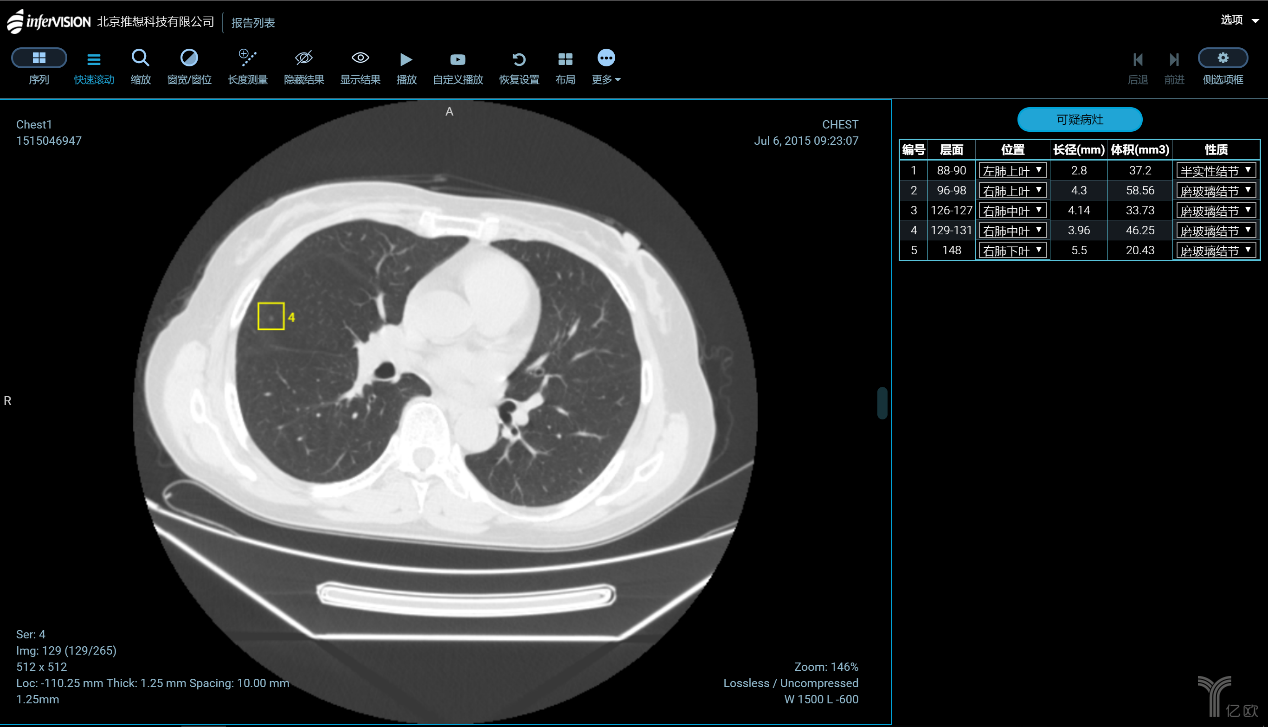

肺結(jié)節(jié)的識(shí)別與診斷,是大部分企業(yè)算法模型訓(xùn)練的起點(diǎn)。一方面是因?yàn)橹袊欠伟┐髧?,肺部影像?shù)據(jù)量最充足;另一方面是由于全球針對(duì)肺結(jié)節(jié)識(shí)別的研究最為成熟。國內(nèi)在肺癌診斷與篩查方向進(jìn)展較快的,主要有推想科技、圖瑪深維、健培科技、體素科技、依圖醫(yī)療、匯醫(yī)慧影、深睿醫(yī)療、視見醫(yī)療、華潤(rùn)萬里云、零氪科技等。除了肺癌之外,針對(duì)乳腺癌、肝癌、鼻咽癌、腦卒中的自動(dòng)檢測(cè)也正在成為焦點(diǎn)。

智能CT輔助篩查產(chǎn)品(AI-CT)功能界面(圖片來源:推想科技)